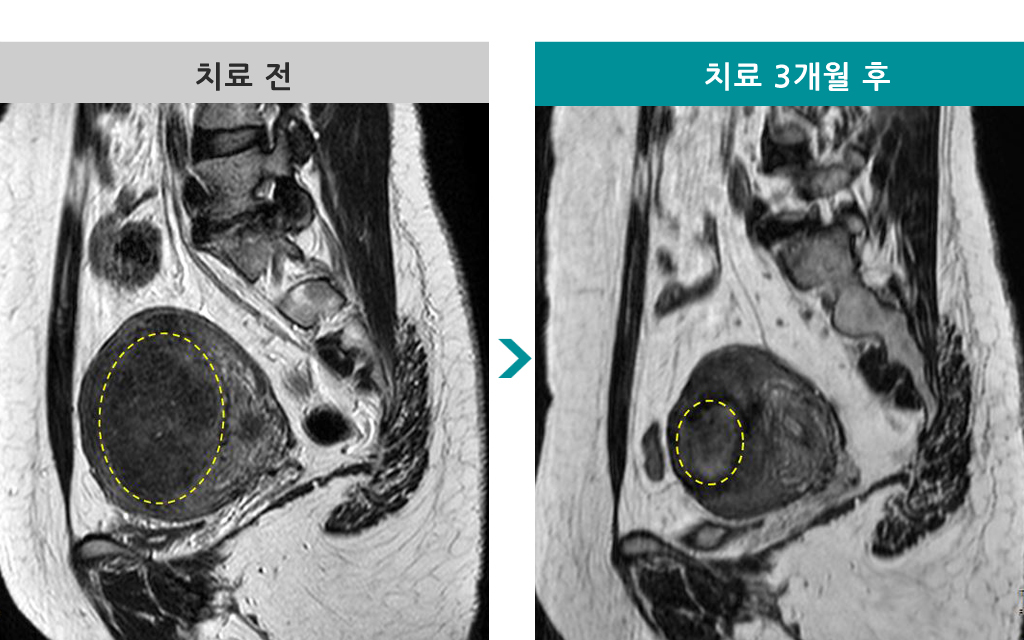

39세 [자궁근종 MR하이푸] 전후 MRI사진 비교 - 3개월 후 용적감소율 88%